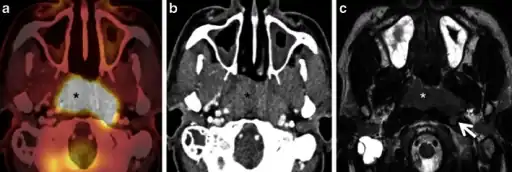

Diagnosis

Classification

Nasopharyngeal carcinoma, also known as nasopharyngeal cancer, is classified as a malignant neoplasm, or cancer, arising from the mucosal epithelium of the nasopharynx, most often within the lateral nasopharyngeal recess or fossa of Rosenmüller (a recess behind the entrance of the eustachian tube opening). The World Health Organization classifies nasopharyngeal carcinoma in three types, in order of frequency: Non-keratinizing squamous cell carcinoma; keratinizing squamous cell carcinoma; and basaloid squamous cell carcinoma.[16] The tumor must show evidence of squamous differentiation, with the non-keratinizing type (also known as lymphoepithelioma) the tumor most strongly associated with Epstein-Barr virus infection of the cancerous cells.[17]

Staging

Staging of nasopharyngeal carcinoma is based on clinical and radiologic examination. Most patients present with Stage III or IV disease.